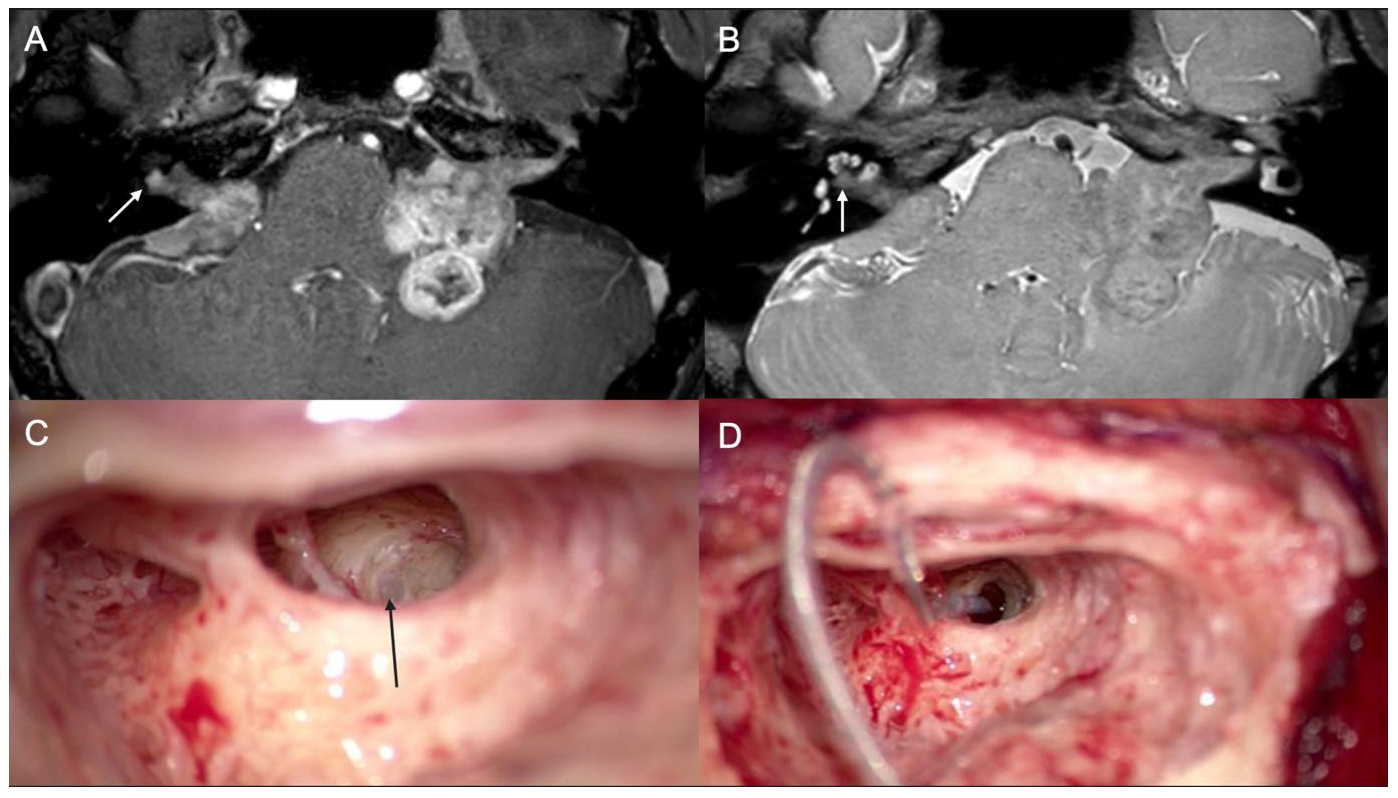

3.1. Case 1